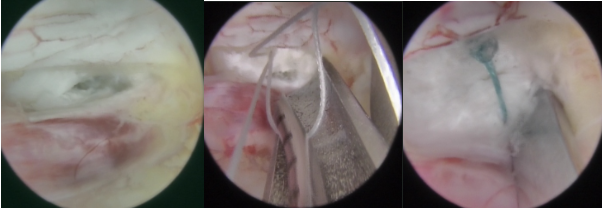

钟炯彪主任为患者实施大通道全脊柱内镜下髓核摘除联合纤维环缝合手术中

有限髓核摘除,椎间盘减压。

纤维环缝合过程,即纤维环缝合前后对照效果。